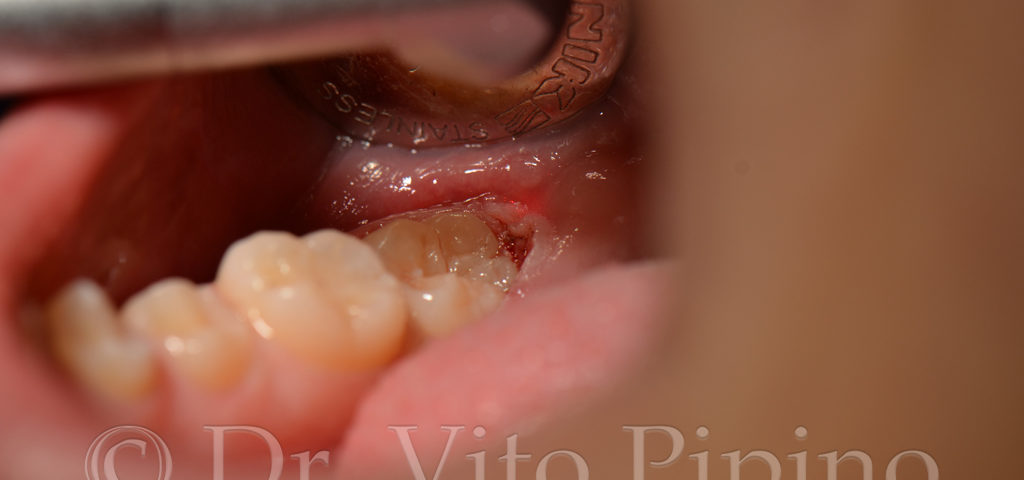

Chirurgia Laser – Caso 1